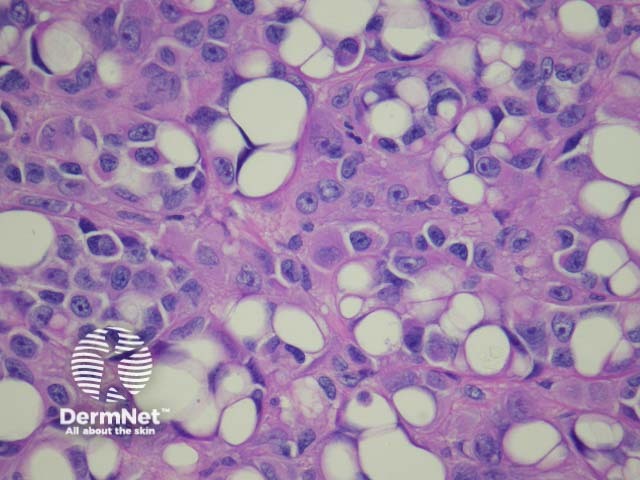

Signet ring melanoma |

Signet ring cells have large pale cytoplasmic globular inclusions, which compress the nucleus (figure 28). |